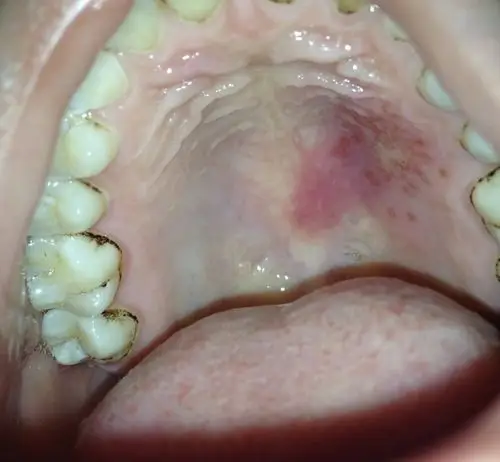

口腔上颚疼痛起泡,总感觉里面好像有水一样舌头顶着会动感觉痛到神经

为什么口腔上颚会这样,该怎么办?